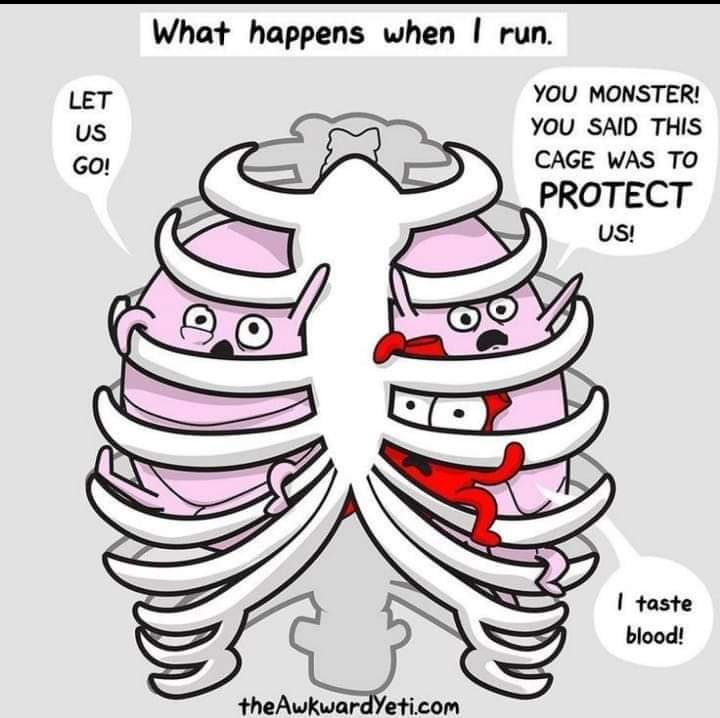

6- بعد تصحيح المعلومة دعنى أخبرك ما الحكمة لكون قلب الإنسان فى منتصف الصدر ؟

الحماية فوجود القلب بداخل القفص الصدرى يحميه من الكثير من الصدمات .تخيل عزيزى أن قلبك فى الكف ستتأذى قلبك فى كل مرة تصافح فيها أحد.

هناك قاعدة تشريحية تنص على أن التكوين يتبع الوظيفة لذلك وجود القلب فى هذا المكان بجانب الرئتين لتبادل الدم يجعل القلب يقوم بوظيفته بصورة أفضل ووجود الرئتين هنا لتكون قريبة من مجرى التنفس وكذلك قريبة من الدماغ.

الحماية فوجود القلب بداخل القفص الصدرى يحميه من الكثير من الصدمات .تخيل عزيزى أن قلبك فى الكف ستتأذى قلبك فى كل مرة تصافح فيها أحد.

هناك قاعدة تشريحية تنص على أن التكوين يتبع الوظيفة لذلك وجود القلب فى هذا المكان بجانب الرئتين لتبادل الدم يجعل القلب يقوم بوظيفته بصورة أفضل ووجود الرئتين هنا لتكون قريبة من مجرى التنفس وكذلك قريبة من الدماغ.